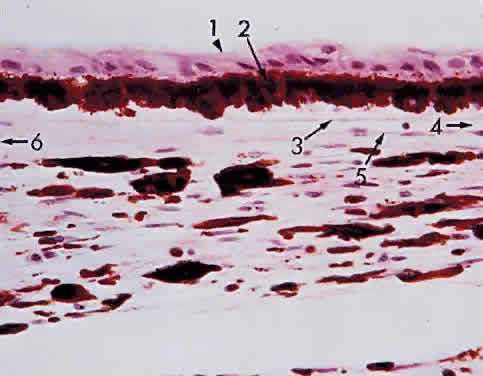

Fig. 3. Brown iris. 1, Anterior dense surface pigmentation;2, thick-walled blood vessel; 3, pigmented epithelium (80% of× 195, KEI 8982B).

Grossly, the iris appears as a ridged diaphragm, measuring about 12 mm in diameter and 0.5 mm in thickness, with a 3-mm, slightly nasal, off-center pupillary aperture in the resting state. The iris is thickest near the collarette and thinnest at the iris root. Therefore, after blunt trauma, the hyphema that occurs usually is due to a tear at the thin iris root: a traumatic iridodialysis. The degree of pigmentation of the iris determines the color of the eye (Fig. 3). The iris appears blue when the stroma is lightly pigmented and brown when the iris stroma is heavily pigmented. Thus, the assessment of “beauty” in eye color is merely an accident of chromatophore (pigment-bearing cell) collection. A portion of the iris in one eye may be heavily pigmented (brown) and the remainder of the iris lightly pigmented (blue). Thus, one eye alone may show color variations, or one eye may be totally blue and the other eye brown (heterochromia iridium).